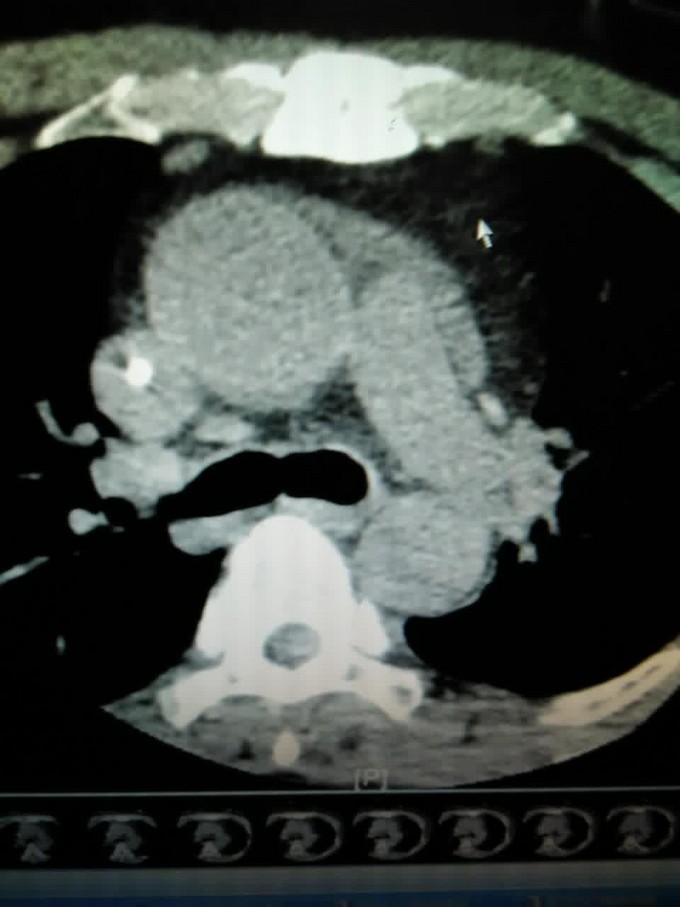

主诉:反复中上腹痛10天 现病史:患者十天前无明显诱因出现中上腹痛,呈持续性钝痛,阵发性加剧,无向腰背部发射,与饮食或体位无明显关系,休息后不可缓解。伴有腹胀、恶心,无呕吐,无反酸,嗳气,没有尿黄,身目黄染,没有发热、畏寒。于当地诊所就诊,诊断为“胃痛”,予药物(具体不详)治疗后疼痛无缓解。遂于罗定市人民医院就诊,住院期间有发热,最高体温不超过39度,小便颜色较前加深,未出现身目黄染。查淀粉酶1700u/L,腹部CT提示:急性胰腺炎并胰周少量渗出,胆囊小结石。诊断为急性胰腺炎,予停留胃管,行ERCP手术未成功,予药物治疗,较前无明显缓解。